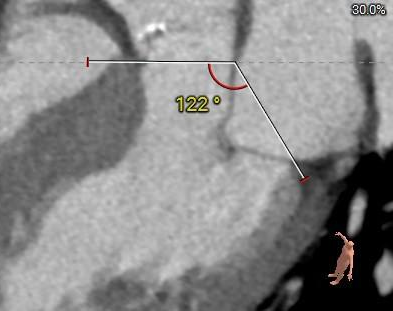

投照角度:

右窦中心

右11足16

左冠切线

左8头13

左右重合

右33足41

主动脉弓角及弓距可,预估输送器可顺利过弓,必要时Snare辅助: